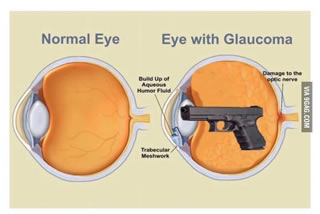

Nell’ambito del World Glaucoma Week, ASL Roma 1 e AIMO hanno organizzato una giornata di screening per la diagnosi precoce del glaucoma. L’appuntamento è per il 14 marzo dalle 8.30 alle 12.30 all’Ospedale Oftalmico di Roma.